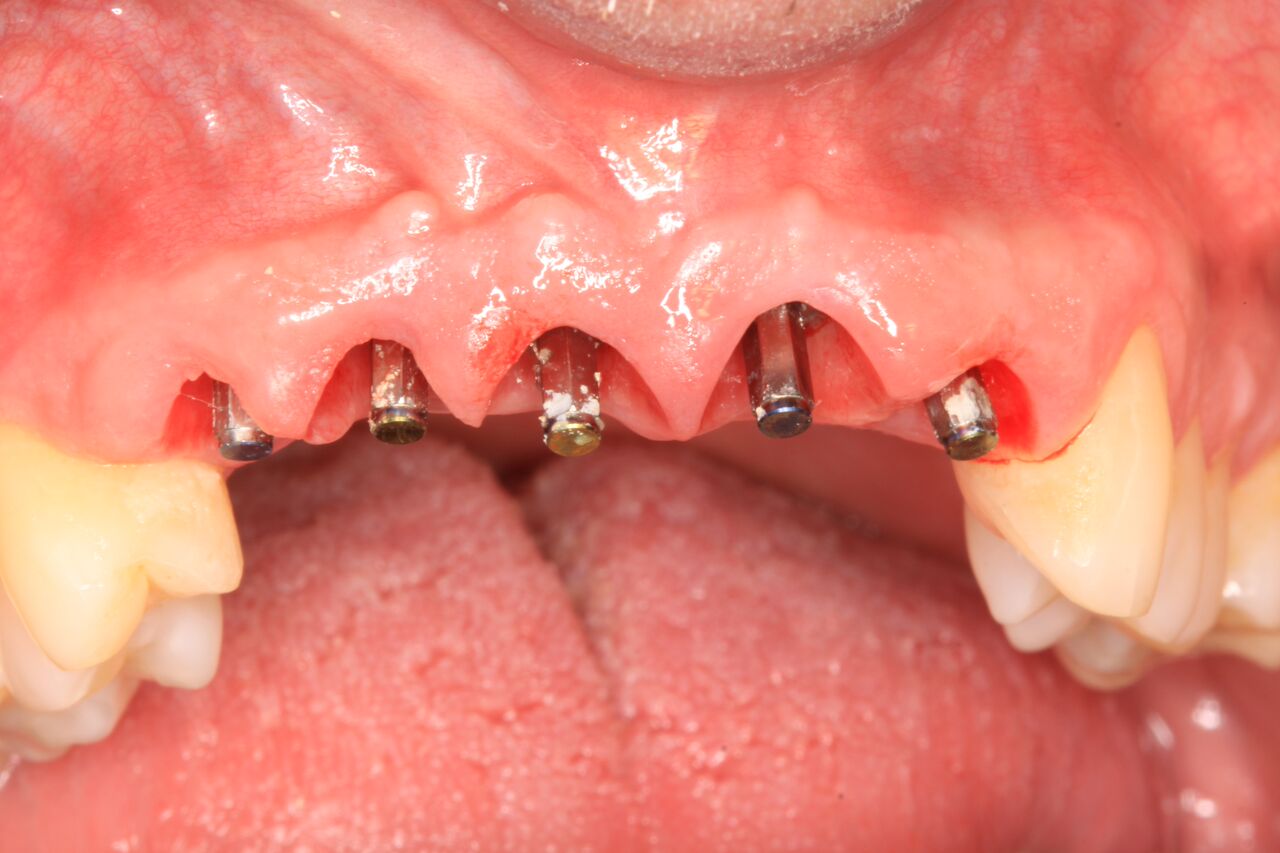

A 42-year-old man presented with a very loose bridge on Nos. 6 through 9 with periodontally compromised retainers on Nos. 6 and 9 (Figure 17 through Figure 19), and endodontically involved No. 10 with a calcified canal. Teeth Nos. 6, 9, and 10 were extracted, the sockets fully debrided, and pontic soft tissue on Nos. 7 and 8 sculpted to be symmetrical in soft tissue contour with the contralateral lateral incisor and central incisor locations. Implants were secured in position Nos. 6 through 10 (Figure 20) in excess of 45 Ncm, the bone was milled to provide unimpeded seating of temporary abutments, and temporary crowns were fabricated chairside and adjusted to be out of occlusion in centric relation and all excursions. The temporary crowns were cemented after extrusion of excess cement extraorally and the patient was prescribed antibiotics, analgesics, and instructed in postoperative care particular to immediately provisionally restored implants. At 6 months, integration was confirmed (Figure 20 through Figure 23) and after placement of scanning abutments, the implants and soft tissues were scanned. Final crowns were fabricated from the scanned images and were cemented after extrusion of excess cement extraorally (Figure 24 through Figure 26), and oral hygiene procedures were reviewed.

(20.) 6-month integration confirmation of Nos. 6 through 10.

Figure 20

(21.) 6-month integration confirmation of Nos. 6 through 10.

Figure 21

(22.) Temporary crowns on Nos. 6 through 10 at integration confirmation.

Figure 22

(23.) Soft tissue maturation at integration confirmation at 6 months.

Figure 23